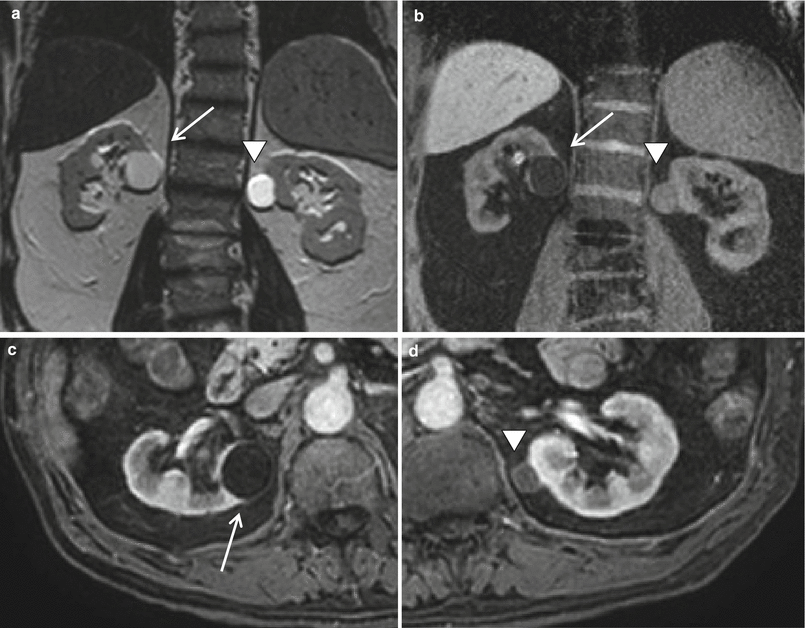

MRI of the kidneys. Axial contrastenhanced T1 fatsaturated Contrast And Kidneys Learn how to reduce your risk. However, in patients with underlying renal. Acute kidney injury (aki) may develop after administration of iodinated contrast material. Contrast dyes used in tests like mris and ct scans can harm kidneys, especially in people with kidney disease. Aki that is related to iodinated contrast material. Mayo clinic health care delivery. Contrast And Kidneys.

Resonance Imaging of the Kidney Radiology Key Contrast And Kidneys Acute kidney injury (aki) may develop after administration of iodinated contrast material. Aki that is related to iodinated contrast material. Mayo clinic health care delivery. However, in patients with underlying renal. Contrast dyes used in tests like mris and ct scans can harm kidneys, especially in people with kidney disease. Learn how to reduce your risk. Contrast And Kidneys.